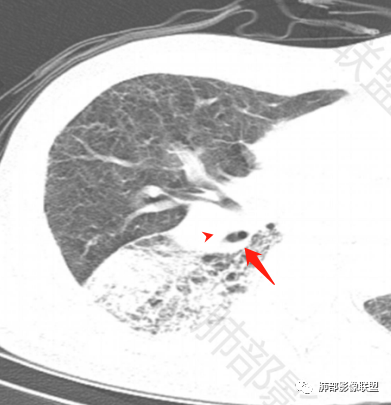

老年男性,反复咳嗽咳痰喘憋8年,加重10天,发热半天。白细胞计数明显升高(存在细菌感染可能),CEA、CA19—9升高(肺癌或间质性肺疾病引起可能)。痰培养见肺克。CT;双肺弥漫小叶间质、中轴间质增厚,胸膜下肺气肿,右肺门及右下叶可见实变影,边界模糊,内支气管走形僵硬,部分见蜂窝样改变,增强后实变区可见低密度区(粘液?),叶间裂膨隆,纵隔及右肺门见肿大淋巴结,右肺门淋巴结内见坏死。存在感染,但单纯感染难以解释支气管走行僵硬、实变内的低密度病灶,考虑恶性伴感染,肺炎性肺癌或黏液腺癌。

2.影像表现:肺气肿背景,右肺下叶呈现明显网格影及蜂窝影、枯枝征,边缘膨隆、叶间裂向前方推移。病灶密度不均,前份见不规则片状实性密度区,实性部分轻度强化,边界不清,周边特征掩盖不清。支气管主要分支显示,呈枯枝征。纵隔窗病灶密度偏低,病灶内血管影边缘稍显模糊,未见明显液化坏死区。

右侧肺门淋巴结肿大,中央低密度;纵隔见轻度增大淋巴结。

3.综合分析:临床方面:慢性病程、急性发作,呼吸道症状伴发热,炎性指标升高,提示存在感染可能;CA199升高,但相对特异性不高。影像双肺气肿,右肺下叶蜂窝状改变明显,夹杂实变密度区,支气管相关但未见阻塞,较常见于感染性病变,如G-杆菌感染等。蜂窝影什么时候出现我们不得而知,实变区周边特征掩盖不清。